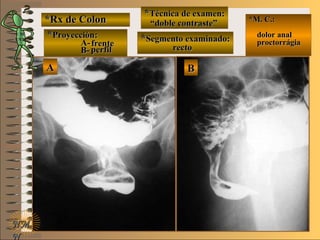

**Técnica de examen:Técnica de examen:

A-A-

B-B- *M. C.:*M. C.:

sin clínicasin clínica

**Segmento examinado:Segmento examinado:

NMNM

E ME M

UNTUNT

BBAA

frentefrente

““doble contraste”doble contraste”

““mucosografía”mucosografía”

panorámica ypanorámica y

cuerpo gástricocuerpo gástrico

A-A-El examen es normal o patológico?El examen es normal o patológico?

Examen normal de estómago panorámico yExamen normal de estómago panorámico y

de cuerpo gástrico con técnicas de : A- doblede cuerpo gástrico con técnicas de : A- doble

contraste (relieve interno fino)contraste (relieve interno fino) , B- mucosogra-, B- mucosogra-

fía (tiene por objetivo reconocer el relieve internofía (tiene por objetivo reconocer el relieve interno

grueso = a pliegues) en proyección de frentegrueso = a pliegues) en proyección de frente